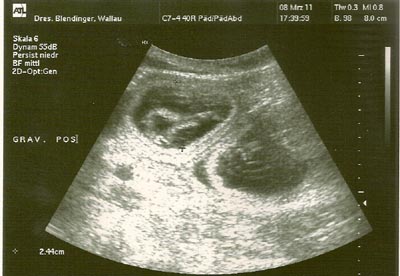

08.03.2011

heute ist der 32.Tag. Es geht Queen supergut. Sie frisst gut und verträgt alles wie immer, sie ist lebendig und zeigt keinerlei Symptome irgendwelcher Nebenwirkungen der Trächtigkeit. Heute waren wir wieder bei Dr. Blendinger. Im Ultraschall sind mindestens 7 Fruchtblasen zu sehen. Eine davon soll im Foto beweisen, dass unsere Queeny Kinder in sich trägt.